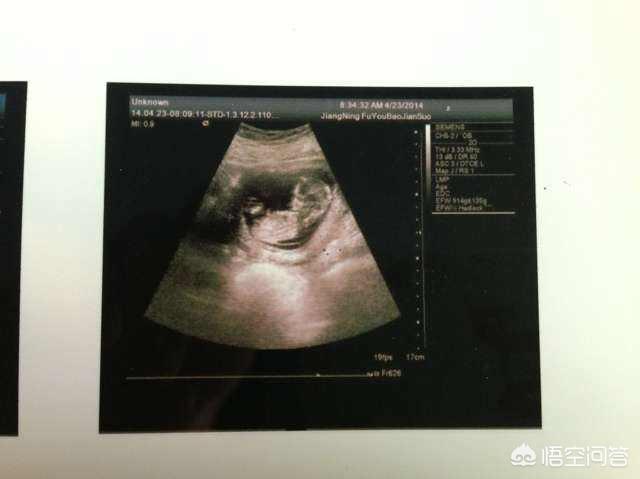

附上一张北京协和医院的B超报告单。显示胎儿的头臀长。